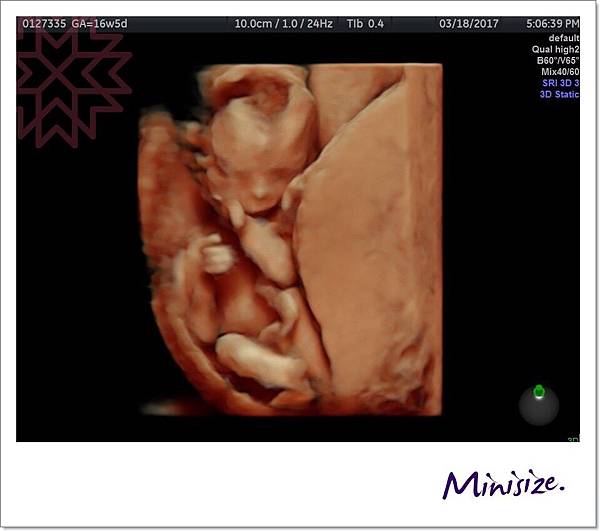

頭圍、頭臀圍、腿長、腦發育、心跳聲、子宮頸長度、羊水是否充足

才了解到原來我的大肚皮裡面藏一個頭臀圍長9.59公分的健康寶寶

聽到寶寶鏗鏘有力的心跳

真的好感動

小生命正在努力地長大中!